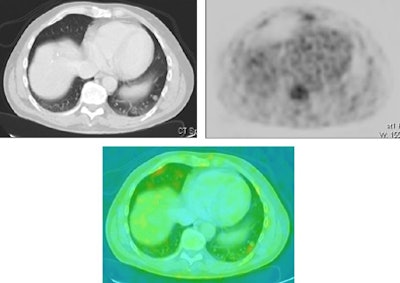

![]() |

| A 48-year-old man with lymphoma. Patient underwent a PET/CT examination for follow-up. CT of the chest was normal. PET examination revealed a hot spot in the right upper lung region that was suspect for lung metastasis. PET-CT showed that this lesion was a bone metastasis, not a lung metastasis. Images courtesy of Dr. Walter De Wever. |